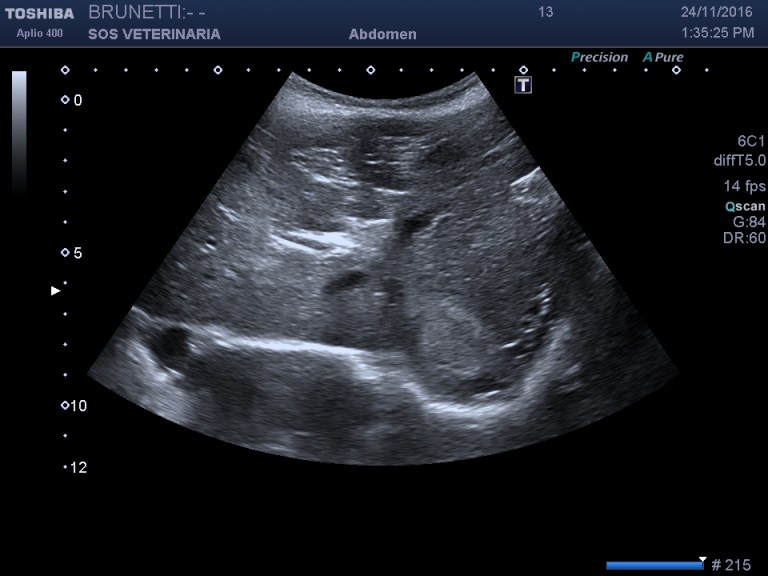

Esame ecografico

massa (circa 6 cm) situata caudalmente verso la coda dell organo eterogena nelle porzioni centrali ,omogena e simile al parenchima sano alla periferia , ben demarcata ,interrompe bruscamente il profilo dell organo,segnali colore doppler moderati non distribuiti omogeneamente e uniformemente

lesione focale ecogena epatica ecogena